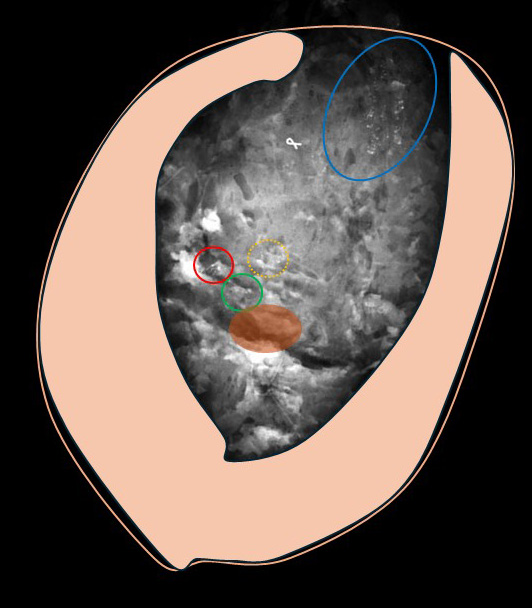

◎石灰化の位置関係

(多発ではなく)同じ乳管系に「複数」存在する石灰化は、実際の乳腺にその位置を落とし込むと、こうなります。

♯青色部分が(前医で)ST-MMTした石灰化で同じ乳管系の中枢側に存在する石灰化が赤緑黄色の3か所の部分

このように一つの「乳管系」があります。

1つの乳管孔の乳管が「枝分かれ」して末梢へ広がっていきます。

乳管内に癌が発生

水色で示した部分の乳管の壁の細胞が癌化

乳管内を癌細胞がどんどん広がる(左図→右図)

更にこのように広がり末梢の枝分かれ部位まで達する

2.石灰化の発生

乳管内に広範囲に広がった癌細胞の「ところどころ」で(乳管内で増殖したために中心部分の癌細胞が周辺から血流が不十分となり壊死に陥る=壊死型石灰化)石灰化発生

これが実際の手術(摘出)標本

石灰化はこのように4か所とも綺麗に切除範囲となり(中心部=青色は乳腺の完全に端まで石灰化あり当然乳腺の端までの切除となります)

乳頭位置は「薄茶色」でしめしており(当然、乳輪乳頭は切除せずに、その裏側の乳腺を乳頭を「超えて」向こう側(下側)まで安全に切除範囲となっています。

↑

あれだけの切除範囲でも、凹むような変形はなく「volumeが全体に減り薄くなる」イメージ